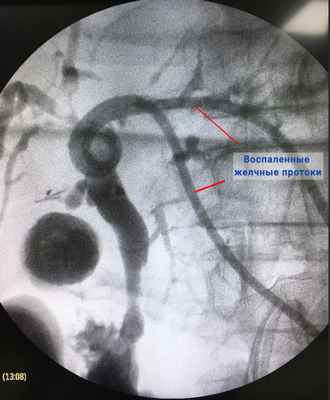

На приеме гастроэнтеролог собирает анамнез, после чего назначает необходимую диагностику. Специалист может предложить пройти УЗИ, гастроскопию, анализы крови, эндоскопическую холангиографию. Обследование выполняется на современном качественном оборудовании импортных производителей: «Stephanix» (Франция), «Olympus» (Япония), «Siemens» (Германия), "Pentax" (Япония).

В рамках диагностики холангита также могут проводиться инструментальные исследования, такие как УЗИ органов брюшной полости, магнитно-резонансная холангиопанкреатография (визуализация желчного пузыря, желчных протоков, печени, поджелудочной железы), эндоскопическая ретроградная холангиопанкреатография, эзофагогастродуоденоскопия (осмотр органов пищеварительной системы при помощи зонда гастроскопа) и др. Методы визуализации позволяют выявить расширения и сужения желчных протоков, установить размеры органов гепатобилиарной системы и получить другие важные диагностические данные. При подозрении на холангит может быть назначена биопсия печени.

- Лучевая диагностика. Включает панкреатохолангиографию – эндоскопическую ретроградную и магнитно-резонансную, ЧЧХГ (чрескожную чреспеченочную холангиографию) с применением контраста. Эти методы исследования помогают визуализировать желчевыводящие пути, увидеть очаг патологии и понять ее причину.